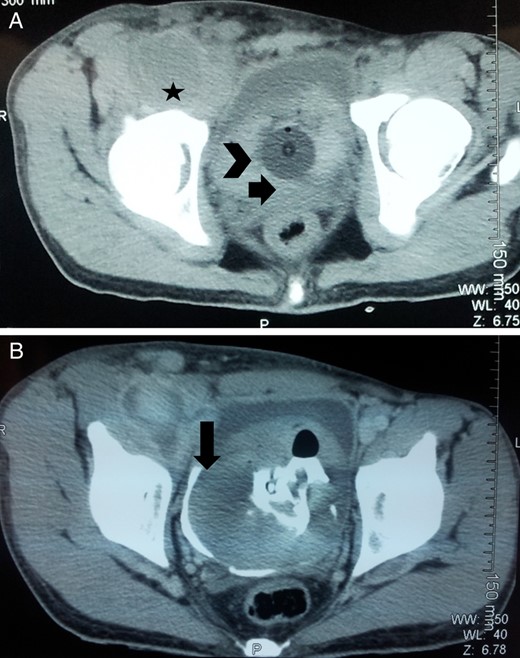

On contrast enhanced CT, a right common femoral pseudoaneurysm of size 12.5 × 6 × 6.5 cm was noted with intra-abdominal extension. Huge clot was also noted in the bladder with no obvious lesion in the kidney, ureter and bladder (Fig. 2). Thus, the patient was planned for exploration of pseudoaneurysm and urinary bladder. On exploration of right groin, there was a huge pseudoaneurysm in the groin extending above the inguinal ligament with 1 l of clot and blood (Fig. 3). Femoral artery was transected and proximal and distal ends were taken into control. Proximal end of femoral artery was ligated, and the leg was examined for distal saturation which was normal, so the distal end was also ligated. After addressing the femoral artery, the urinary bladder was explored. A small rent (∼0.5 × 0.5 cm) was noted in the right lateral wall of the bladder which was communicating with the wall of the pseudoaneurysm along with 2 l of blood and clot in the bladder. Thus, the enigma of hematuria was solved. Bladder was repaired according to standard technique and drain was kept in retroperitoneal space and abdomen was closed.

Axial CECT abdomen and pelvis pmages: (A) femoral pseudoaneurysm (marked with star), urinary bladder with clots (arrowhead) and Foley's catheter in situ (arrow); (B) communication between pseudoaneurysm and urinary bladder which was overlooked preoperatively (marked by arrow).